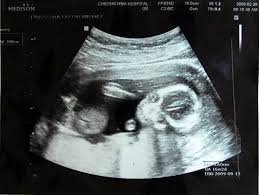

하지만 막상 아이가 들어섰다는 생각을 하면 어떻게 해야할 지 몰라 당황하는 경우가 많다. 이것이 임신 초기증상이 맞는지 아니면 단순한 체기인지 헷갈릴 때도 많다.

임신 1주차 증상은 생리가 늦어지고 속옷에 착상혈이 묻는다. 또한 질 분비물이 많아지기 시작한다. 임신 2주차 증상으로는 가슴이 아프고 커지며 자주 소변이 마렵고 열감이 느껴지기도 한다. 감기로 착각하는 경우들도 많다. 임신 3주차 증상은 2주차와 거의 동일하지만 점점 심해진다.